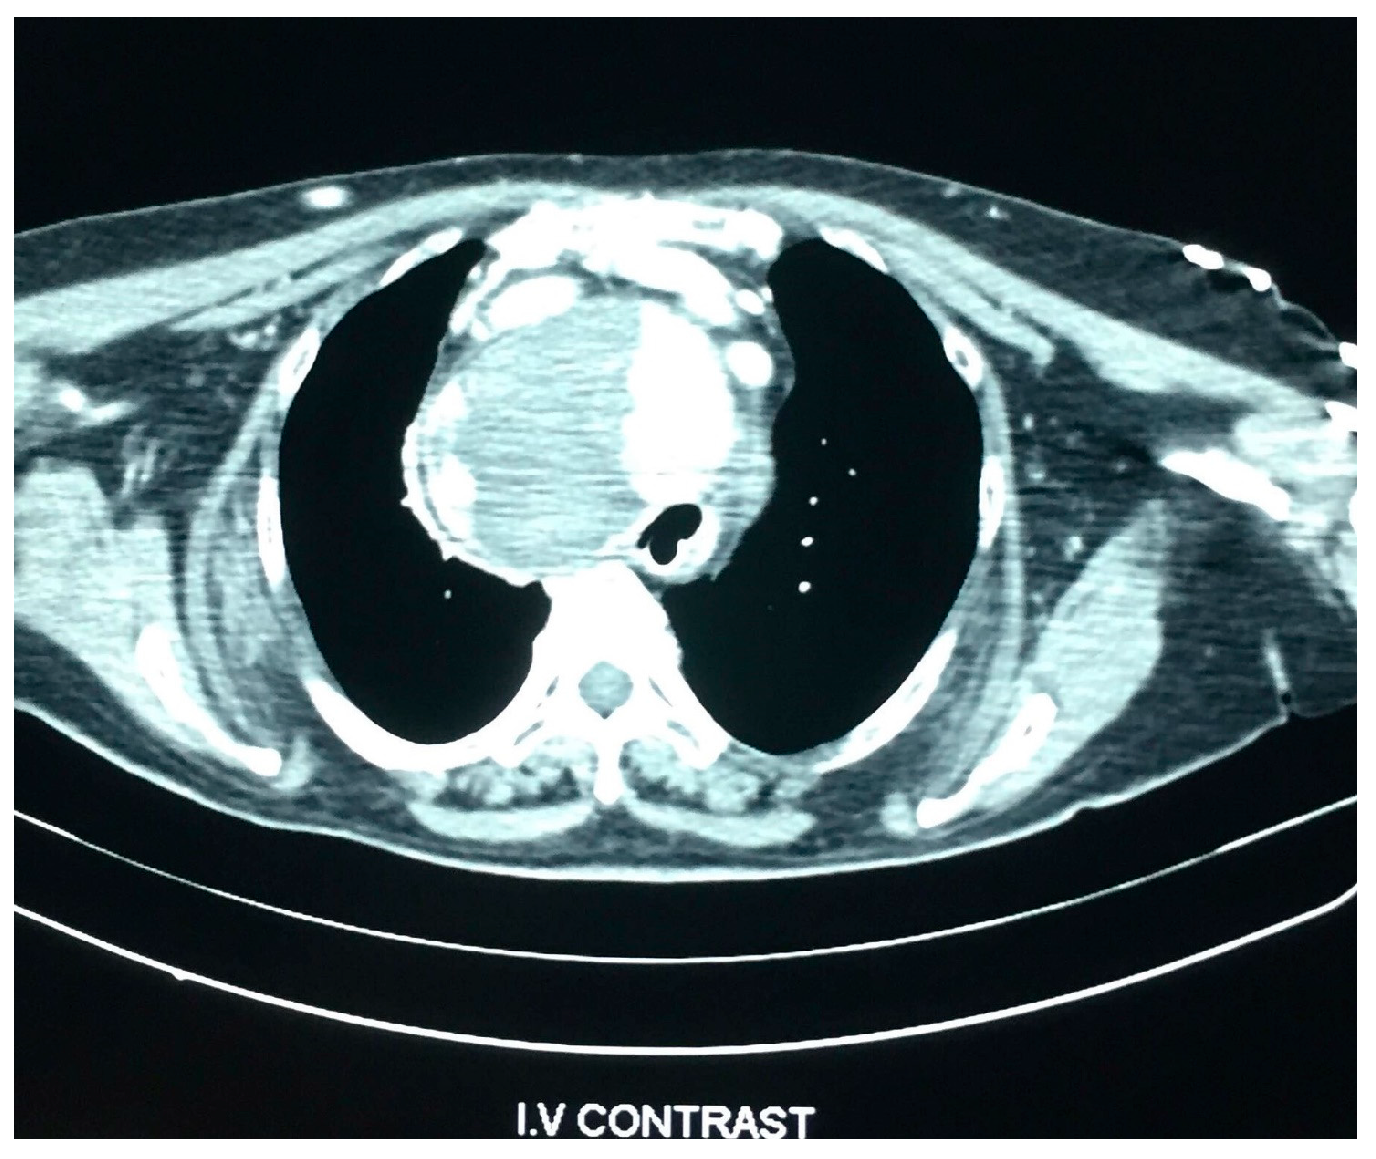

Cardiopulmonary Arrest Caused by Large Substernal Goiter—Treatment with Combined Cervical Approach and Median Mini-Sternotomy: Report of a Case

Koulouris, C.; Paraschou, A.; Manaki, V.; Mantalovas, S.; Spiridou, K.; Spiridou, A.; Laskou, S.; Michalopoulos, N.; Radu, P.A.; Cartu, D.; et al. Cardiopulmonary Arrest Caused by Large Substernal Goiter—Treatment with Combined Cervical Approach and Median Mini-Sternotomy: Report of a Case. Medicina 2021, 57, 303. https://doi.org/10.3390/medicina57040303